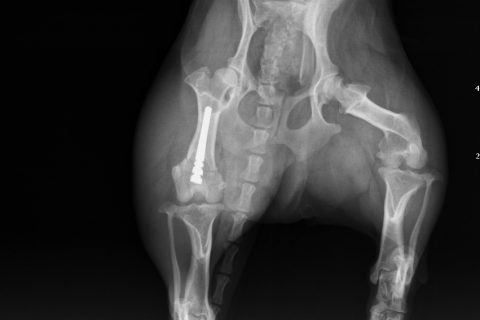

症例:大腿骨先端の骨折

今回は、大腿骨の先端が骨折した症状です。

専門的には、大腿骨遠位端骨折といいます。

この骨折は比較的珍しい骨折ですが、今回は滑車溝の真ん中で骨折した非常に珍しい骨折です。

大腿骨遠位端骨折は、比較的手術が難しい骨折です。当院では院内で矢状ピンを作成して手術しています。

治療結果はかなり良い状態です。